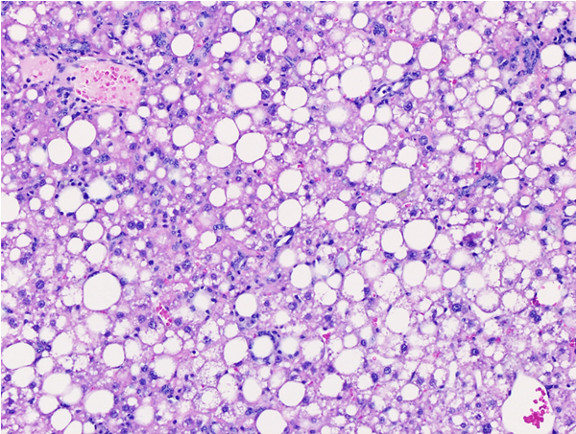

Figure 6: Histopathology for C57BL/6NTac mice placed on D09100310 diet (MASH B6NTac) or kept on chow diet (Control B6NTac) from 6 weeks of age. Animals were on diet for 27, 35 or 53 weeks. Hematoxylin and eosin (H&E) staining illustrates morphological changes including steatosis and infiltration of immune cells. Activated HSCs were identified in liver sections by using a rabbit polyclonal antibody to alpha-smooth muscle actin (a-SMA) (1:500 dilution; ab5694; Abcam, Cambridge, MA) which was detected by an anti-rabbit IgG embedded polymer with embedded horseradish peroxidase and visualized with 3,3′-diaminobenzidine (DAB) chromogen (Agilent, Carpentaria, CA). Hepatocellular lipid droplets were identified by visualization of the lipid-binding protein adipophilin known to be expressed in steatotic livers. Sections of livers were probed using a rabbit polyclonal anti-adipophilin antibody (1:200 dilution; NB110-40877, Novus Biologics, Littleton, CO) which was detected by an anti-rabbit IgG embedded polymer with embedded horseradish peroxidase and visualized with 3,3′-diaminobenzidine (DAB) chromogen (Aligent, Carpentaria, CA). Picrosirius red (PSR) staining illustrates collagen I and III fibers and is used to measure fibrosis. The same individual MASH or control animal is shown for all four stains in a particular time point. Different individual animals were used for each time point (i.e. data is not longitudinal by animal). Histopathology services provided by IDEXX BioAnalytics.

C57BL/6NTac mice either on MASH diet D09100310i or on control NIH-31M chow diet were necropsied at 22 (MASH only, no controls), 33, 41 or 59 weeks of age. With the exception of the 59 weeks of age group, MASH mice were selected as two full cagemate groups (10 total mice, 5 mice/cage). A portion of liver was collected for histopathology analysis. The remainder of the liver was dissected and any gross lesions or abnormalities were noted.

General MASH mouse findings: All mice were bright, alert and responsive. Fur coat condition was visibly oily and all mice had body condition score 5/5. Alopecia/barbering was evident in some mice, as were healed fight wounds. All animals had marked mesentary and subcutaneous adipose tissue. Liver in all mice was grossly pale to tan, smooth, and uniformly enlarged. All mice displayed moderate diffuse hepatomegaly with steatosis. For nearly all mice, no masses or lesions were observed on serosal or cut side of livers.